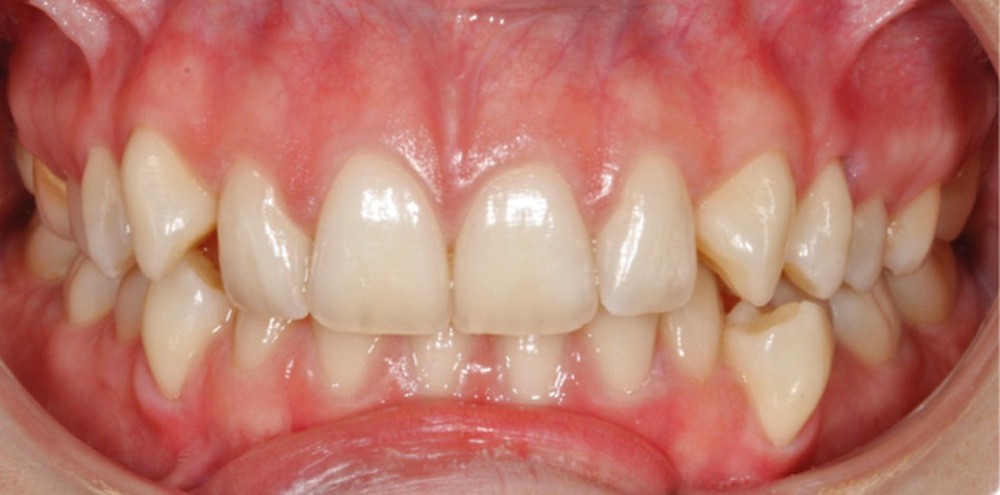

L’examen intra-arcade met en évidence une hygiène bucco-dentaire irréprochable, favorable à un traitement en technique linguale. Le phénotype parodontal est fin dans la région incisivo-canine mandibulaire. L’encombrement est estimé à 8 mm à la mandibule et à 4 mm au maxillaire (fig. 1). Les arcades ont des formes similaires, en U. Les rapports inter-arcades mettent en évidence une classe 1 d’Angle molaire, une classe 2 d’Angle canine et une supraclusion antérieure (recouvrement : 5 mm ; surplomb diminué). Les milieux inter-incisifs sont déviés entre eux avec une origine mixte (= 1,5 mm) (fig. 2).